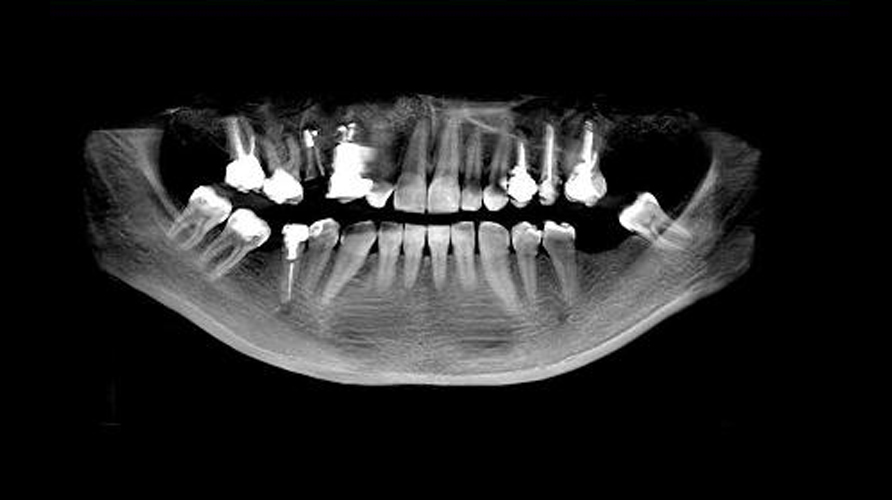

Imagistica dentară presupune realizarea de investigații precum radiografii sau scanări digitale pentru a vedea în detaliu dinții, rădăcinile și osul maxilar. Acestea ajută la depistarea problemelor ascunse, cum ar fi carie dentară, infecții sau afecțiuni osoase. Informațiile obținute sunt esențiale pentru stabilirea unui diagnostic corect și a planului de tratament.